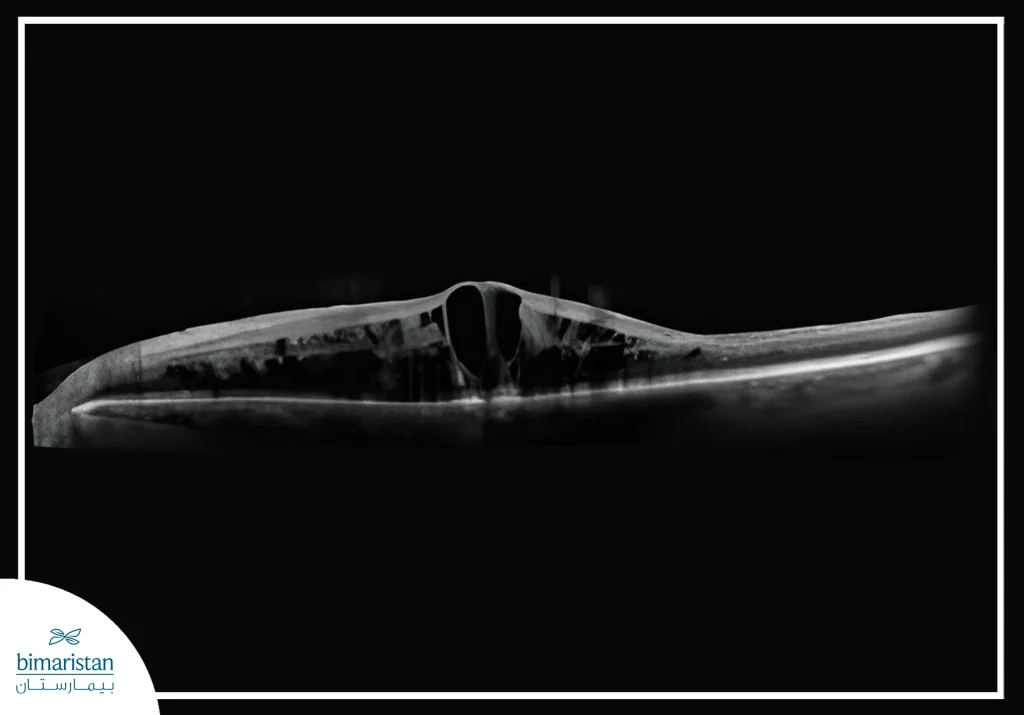

2. Optical coherence tomography

One of the most important modern tests for retinal evaluation, it detects the edema of the yellow smudge caused by the accumulation of fluid in the center of vision and accurately measures the thickness of the retinal layers, and helps follow the progression of the condition and the patient’s response to injection or laser treatment.